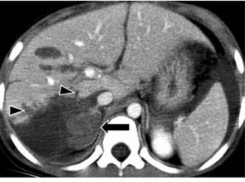

- Tụ máu trong nhu mô: tổn thương tăng tỷ trọng tự nhiên từ 60 – 80 UH, sau khi tiêm thuốc cản quang vùng này không thay đổi tỷ trọng. Trung tâm của vùng

đụng dập có thể chứa khối máu tụ và vùng này sẽ tăng tỷ trọng ngay sau khi bị chấn thương. Tỷ trọng khối máu tụ cũng thay đổi theo thời gian [21].

Hình 1.9: Tụ máu trong nhu mô trước và sau tiêm cản quang (mũi tên).

Nguồn: Shanmuganathan K, Mirvis SE [21].